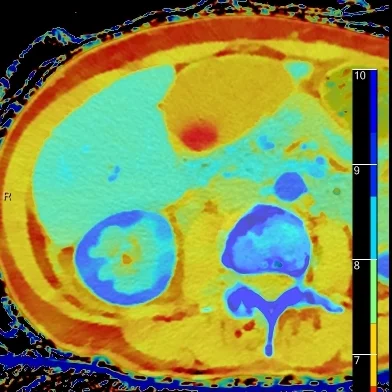

Overlay Z-effective image shows the renal cortical defect very well, but note a gallstone now pops into view!